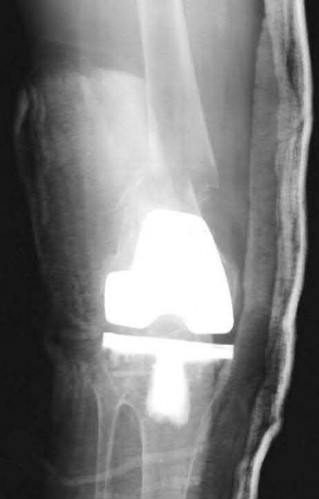

Question 16:

A 65-year-old man presents with anterior knee pain and a feeling of instability during stair climbing 1 year after a primary total knee arthroplasty. Examination reveals a lateral patellar tilt. CT scan is performed to evaluate component rotation. Which of the following errors in component positioning is most likely responsible for his symptoms?

Correct Answer: Internal rotation of the femoral component

Explanation:

Internal rotation of the femoral component or the tibial component increases the Q angle, leading to lateral patellar maltracking, lateral patellar tilt, and anterior knee pain. External rotation of the components generally improves patellar tracking.